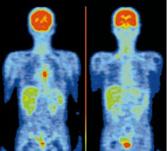

利用高能射线的超强穿透能力,由闪烁材料组成的探测器可广泛应用在高能物理与核物理实验、影像核医学(Computed Tomography ,简称 CT和Positron Emission Tomography ,简称 PET )、工业CT在线检测、油井勘探、安全稽查及反恐应用等许多领域,是一种生产生活密切相关的功能材料。

图2 闪烁材料在核医学成像PET仪器上的工作原理